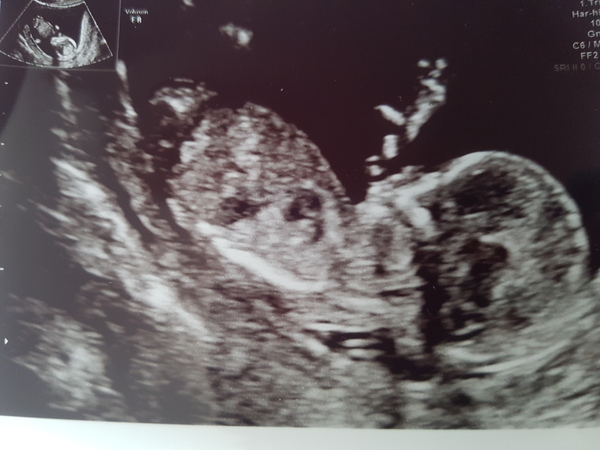

Hi guys don't think I've posted on this thread before! Had my 12 week scan today and I'm 13 weeks exactly. There's a couple of questions I had so hope you don't mind me asking and apologies for the long post! Firstly with my first, a boy, I did the combined test and got a high risk downs result. Had a CVS and thankfully he was all fine. It transpired I had a very low Papp-A (some kind of protein in pregnant women's blood I believe) so even though he was healthy they said he might stop growing at 20 weeks or have growth issues. After that I was scanned regularly but he was fine and born 5 days early weighing 7lb 11. I opted for the combined test again today but worried they'll ring tomorrow to say I'm high risk again - as I was last pregnancy does that mean I'm likely to be high risk this pregnancy?

Secondly, this is more light hearted, I've heard the nub theory/test is good for predicting gender before the second scan. The top pic is my first born who's a boy and the second pic is the scan I had today. What do you reckon? I'm thinking another boy? I'm not bothered either - expecting a boy as no girls in my family for years - but baby being healthy is the most important thing!